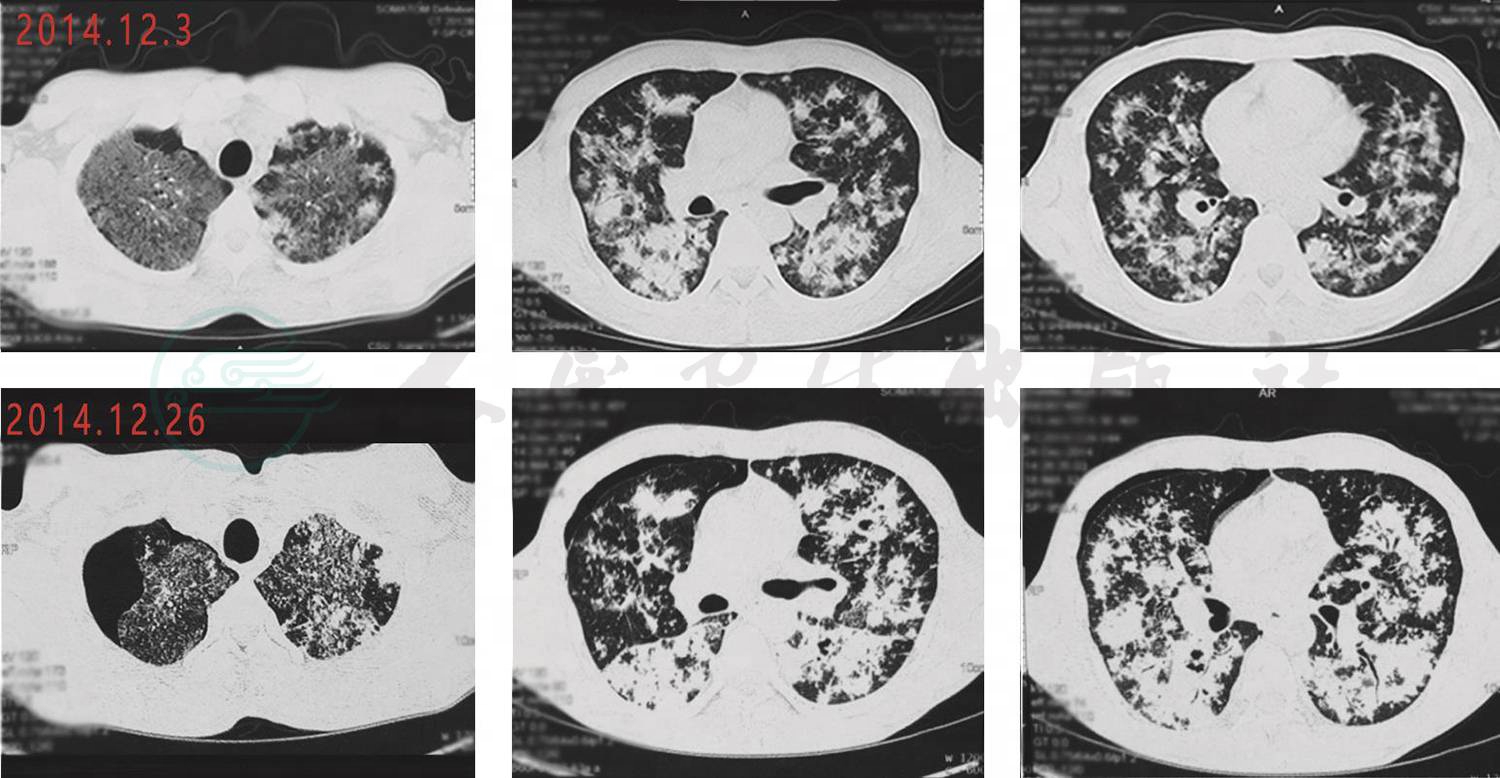

6.2014年12月26日复查胸部CT(图5)对比2012年12月3日老片,抗结核过程中双肺病变较前进展,双上肺及右下肺病变新增空洞样病变。

图5 胸部CT

(2014年12月26日与2012年12月3日对比)